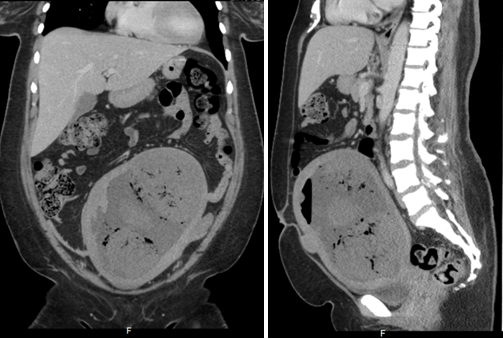

Patients Chest X-ray revealed normal findings. Pelvic ultrasound (Figure 1) showed enlarged uterus 16.9 cm x 10.59 cm x 4.95 cm with heterogeneity compatible with a history of multiple large leiomyomas. There were multiple dirty shadows with ring down densities suggestive of air within the uterine parenchyma. A loculus of fluid within the uterus was also noted (Figure 1). Abdominal CT imaging (Figure 2) (Figure 3) confirmed an enlarged lobular uterus. There were heterogenous multilobular masses with decreased attenuation and numerous foci of internal gas. Findings were most consistent with a necrotic fibroid, lesion measured 20 x 11.4cm. Gas was present within the lesion anteriorly and findings consistent with fluid rather than soft tissue density seen within the adjacent portions of the lesion (Figure 2) (Figure 3). No free intraperitoneal air was noted. Patient was soon after admitted to the Gynecology service with a diagnosis of Pyomyoma.

Figure 3 Patient Number 1, Computerized Tomography of Abdomen and Pelvis, coronal and sagittal view: Enlarged heterogenous multilobular masses within uterus, measuring 20 x 11.4 cm, consistent with Infarcted fibroid after embolization with internal gas, air and debris as expected after uterine artery embolization (UAE).